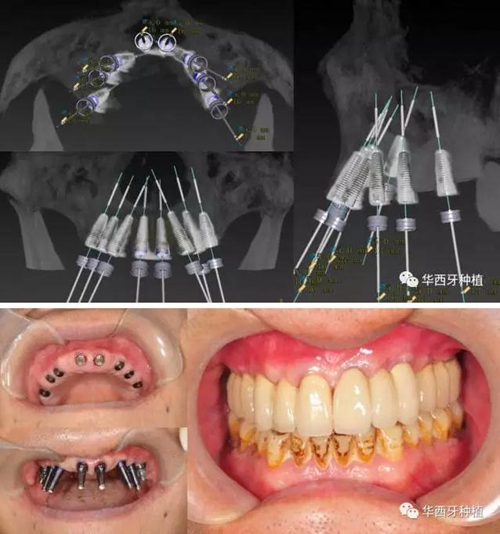

吳教授提到了使用數(shù)字化建模與導(dǎo)板的聯(lián)合應(yīng)用,不僅可以從設(shè)計上降低修復(fù)難度,便于在修復(fù)為導(dǎo)向的設(shè)計中種植體方向的確定,同時可以加入微創(chuàng)的手術(shù)方法,減輕術(shù)中創(chuàng)傷。

對于傳統(tǒng)的all-on-four術(shù)式,吳教授加入了微創(chuàng)的指導(dǎo)思想,設(shè)計時同樣加入數(shù)字化三維重建與修復(fù)一體化設(shè)計,增加了手術(shù)的可控性,同時極大減輕了患者的創(chuàng)傷程度,縮短了修復(fù)周期。